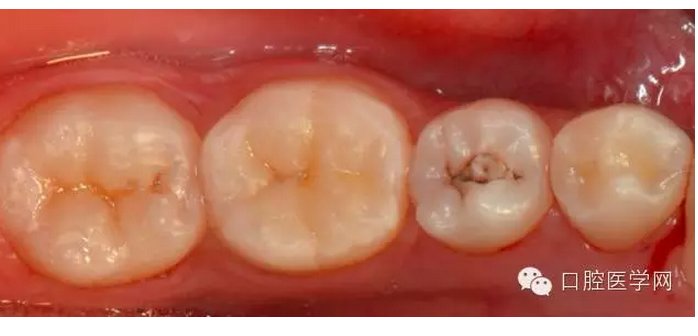

今天把一例后牙區(qū)樹脂直接填充與大家分享,希望對(duì)您有幫助。

術(shù)前照一定要清晰完整,對(duì)于窩洞制備后的he面填充有參考意義。